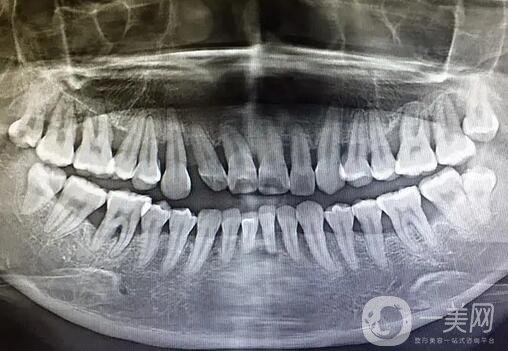

牙槽骨修整術(shù)是口腔外科常見的門診手術(shù)。其目的是去除阻礙義齒修復的部分,使牙槽嵴均勻承受咬合壓力,從而恢復咀嚼、語言、五官等口腔頜面功能。由于手術(shù)對象多為老年求美者,因此更應重視術(shù)前心理護理、術(shù)中密切配合及術(shù)后教育。

局部麻醉用于外科手術(shù)麻醉。對于牙槽骨上孤立的小骨尖,可用鈍器墊紗布,直接打入牙槽骨。對于輕度上頜前突,拔牙后可去除牙槽嵴隔,可鑿除唇側(cè)骨板并壓向舌側(cè)進行矯正,對于重度上頜前突,應根據(jù)前突情況切除唇側(cè)骨板、牙槽嵴隔及部分腭側(cè)骨板,然后切除軟組織并縫合嚴密。其他需要手術(shù)的病例,可采用矯正小范圍修剪作為牙槽骨底部的弧形切口;拍打;去骨;銼骨面;洗去骨屑,粘膜恢復后間斷或連續(xù)縫合傷口,7日拆線。

牙槽骨修整術(shù)的適應癥

1.義齒基托下方牙槽嵴突出嚴重;

2.拔牙后牙槽骨吸收不充分,留下尖銳的骨緣或膨出;

3.上下頜間隙過小,義齒難以戴上;

4.前牙牙槽骨過度突出,妨礙義齒建立正常牙齒,有礙美觀;

5.對于義齒修復者,拔牙后應同時修整牙槽嵴,使其平整自然。